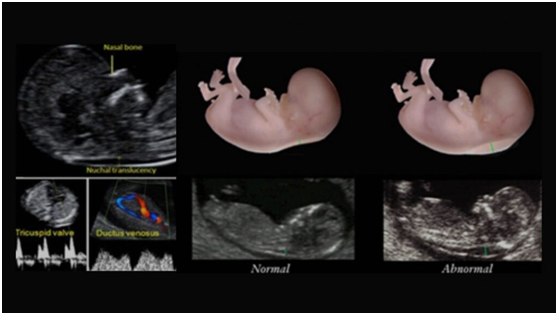

என்.டிஸ்கேன் (Nuchal Translucency Scan) என்பது குழந்தையின் குரோமோசோமால் அசாதாரணங்களால் ஏற்படும் எந்தவொரு கட்டமைப்பு குறைபாடுகளையும் நிராகரிக்க செய்யப்படும் அல்ட்ராசவுண்ட் ஸ்கேன் ஆகும். நியூக்கல் ஸ்கேன் என்பது குழந்தையின் கழுத்துக்குப்பின்னால் திரவம் நிறைந்த இடம்.என்.டிஸ்கேன் இந்ததிரவ இடத்தையும் குழந்தையின் நாசிஎலும்பையும் சரிபார்க்கிறது. நாசிஎலும்பு என்பதுகுழந்தையின் மூக்கின்நுனிக்கு இடையில்காணப்படும் ஒரு பிரகாசமான எக்கோஜெனிக் இடைவெளி.

கருமருத்துவ நிபுணர்கள் டவுன்சிண்ட்ரோம் நோய் அறிகுறியின் அபாயத்தை மதிப்பிடுவதற்கு நியூக்கல் ஸ்கேன் (உங்கள் குழந்தையின் கழுத்தின் பின் புறத்தில் தோலின் கீழ் திரவத்தின் தொகுப்பு) மற்றும் கருவின் நாசி எலும்பைச் சரிபார்க்கிறார்கள். இந்ததிரவத்தின் அளவீடு நியூக்கல்ட்ரான்ஸ்லூசென்சி (Nuchal Translucency) அளவீடு என்று அழைக்கப்படுகிறது.

கருவில் இருக்கும் அனைத்து குழந்தைகளுக்கும் இந்த இடத்தில் சிறிது திரவம் இருக்கும். இருப்பினும், குரோமோசோமால் அசாதாரணங்கள் அல்லதுபிற உடல்நலக்கவலைகள் கொண்ட கர்ப்பங்கள் அதிகரித்த திரவத்தைக்காட்டுகின்றன. தவிர, இதனுடன் நாசிஎலும்பு இல்லாத நிலையும் ஏற்படலாம்.